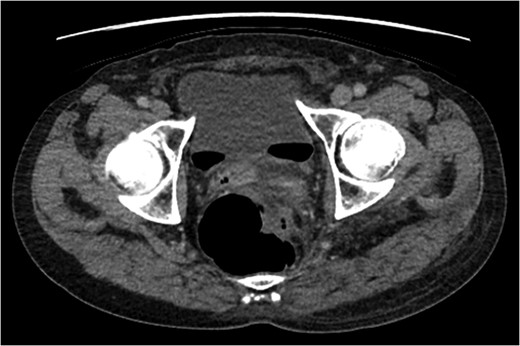

A rare complication of diverticular disease is the formation of fistulas, most commonly either colo-vesical or colo-vaginal. We present the unusual case of a perforated sigmoid diverticulum forming a colo-gluteal fistula and presenting initially as a gluteal abscess in an otherwise asymptomatic patient. After drainage of the gluteal abscess, the patient re-presented with faecal loss from the abscess drainage site. Imaging revealed fistulous communication between the sigmoid and the left obturator internus muscle, tracking to the gluteus maximus with associated abscess and cutaneous communication to the site of previous drainage. The patient underwent an emergency Hartmann's procedure with lay open/abscess drainage of the gluteal cavity. Post-operatively the patient experienced continuing discharge from the gluteal fistula despite repeated drainage and debridement causing considerable morbidity, inconvenience and misery. Clinicians should maintain a high index of suspicion when presented with a gluteal abscess and should consider the possibility of an intra-abdominal source.

The patient re-presented a week after discharge, complaining off persistent pain around the buttock, with feculent discharge and flatulence from the wound. Abscess cultures from the previous admission were reviewed and noted to have grown Escherichia coli and clostridium species.

An emergency Hartmann's procedure was performed under general anaesthetic through a lower midline incision as well as lay open of the perineal fistula. On opening the abdomen, a perforated diverticulum was identified extending into the left lateral pelvic wall. A standard Hartmann's procedure was performed, with sigmoid colectomy, division of rectum at recto-sigmoid junction and a tension-free stoma formed in left hypochondrium. The left buttock abscess cavity extended by a further 2–3 in. and the cavity then packed.

Following the operation, the patient had a short and uncomplicated critical care stay and was subsequently discharged. He has since continued to experience ongoing discharge from the fistula with follow-up imaging showing a reduction in the size of the abscess cavity but continuing patency of the fistula tract, despite repeated wound debridement and packing, drainage of the fistula and rectal washout.